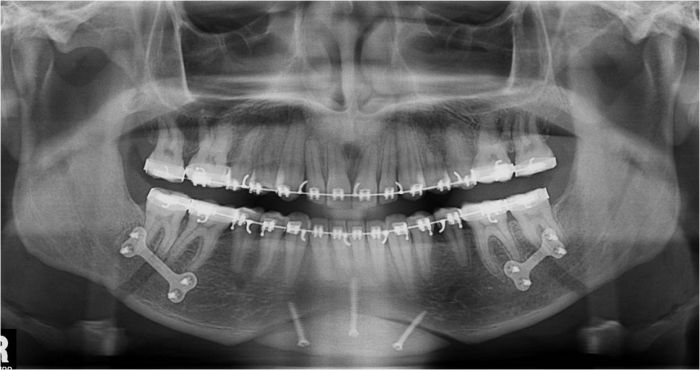

Raio X inicial